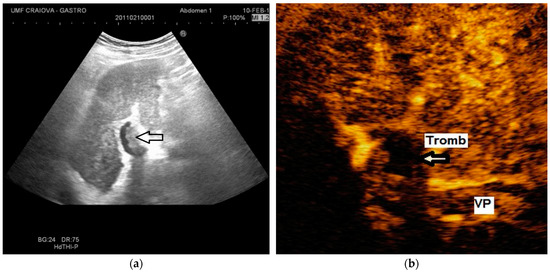

The diagnosis of PVT and PC is made by imaging procedures (transabdominal ultrasound with a Doppler or contrast-enhancing computed tomography scan, magnetic resonance imaging, or angiography in the case of therapeutic intended procedures) [1,3,12,13,14,21,29]. Transabdominal ultrasound is a reliable procedure in 60–100% of cases, with an anechoic aspect in recent cases (requiring Doppler examination or CEUS) and a hypoechoic or hyperechoic aspect in chronic cases [22,29]. Doppler examination may show an anechoic or hypoechoic thrombus and a slower (<15 cm/sec) or absent portal blood flow, and is considered the gold standard (color Doppler) for the diagnosis of PC [1], with a sensitivity and specificity of 95% (Figure 1 and Figure 2) [22]. CEUS can help the diagnosis of benign or malignant PVT, can characterize associated focal liver lesions [30], allows a better characterization of PVT [31], and also permits better detection of PC—Figure 3 and Figure 4 [32]. CT scan and MRI (Figure 5 and Figure 6) are more accurate for the evaluation of liver causes (HCC, abscesses, and other tumors) or other local causes (pancreatitis, diverticulitis, and appendicitis), and for complications (bowel infarction or perforation), and may show permeability of the portal venous system and the flow direction [1,22]. Malignant PVT has intra-thrombus arterial signals on CT, MRI, and/or CEUS, with portal vein diameter frequently 23 mm or above, and with the presence of the tumor at imaging examination (Figure 4 and Figure 6) [21].

Figure 1.

Portal cavernomatous transformation. (a) Multiple serpiginous echo-free structures (vessels) replacing the normal portal vein are seen in B-mode at the hepatic hilum; (b) Color Doppler examination confirms the presence of venous flow within the vessels of the cavernoma.

Figure 2.

Portal cavernomatous transformation. (a) Portal vein cannot be identified; instead, meandering venous branches are visible in the porta hepatis, indicating portal vein thrombosis and consequent cavernous transformation. (b) Power Doppler ultrasonography identifies flow within the vessels.

Transabdominal ultrasound with Doppler protocol (Figure 1a,b and Figure 2a,b), CT scan (Figure 3a,b), and MRI (Figure 4a,b) were used for the diagnosis in 88.9, 75.1, and 15% of cases, respectively. CEUS was used for the diagnosis in 49 cases (25.9%) but in only 29 cases was it used for the evaluation of the thrombus, and in two cases for cavernoma diagnosis (Figure 5a,b and Figure 6a,b).